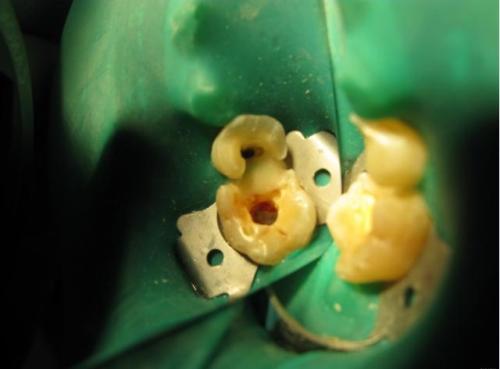

牙髓炎圖片